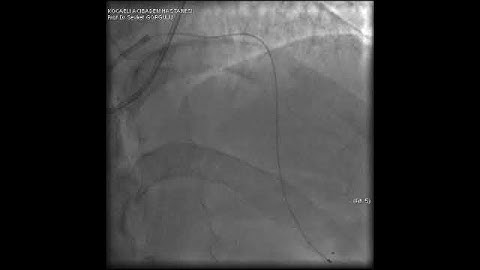

Microcatheter Tip Fracture During LAD CTO PCI: A Complication Video 3